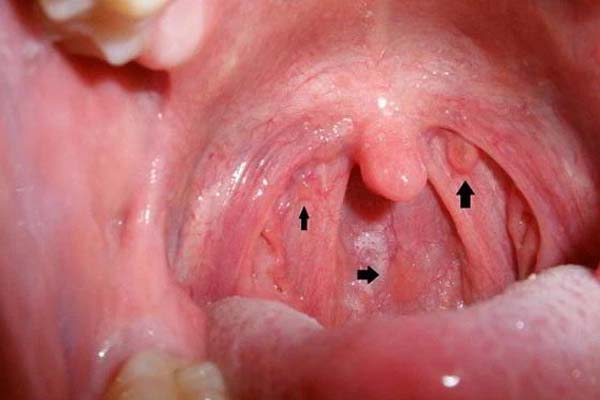

Công dụng đầu tiên của vỏ bưởi là hỗ trợ điều trị các tình trạng về đường hô hấp ở cả người lớn lẫn trẻ em nhờ vào các thành phần dược liệu có trong vỏ bưởi. Nếu bạn đang bị ho, gắt cổ hoặc viêm họng hãy lấy 50 gram vỏ bưởi thái nhỏ rồi phơi khô, sau đó đun sôi cùng với 100ml nước. Uống nước vỏ bưởi vài lần mỗi ngày sẽ giúp bạn cảm thấy thoải mái hơn rất nhiều.